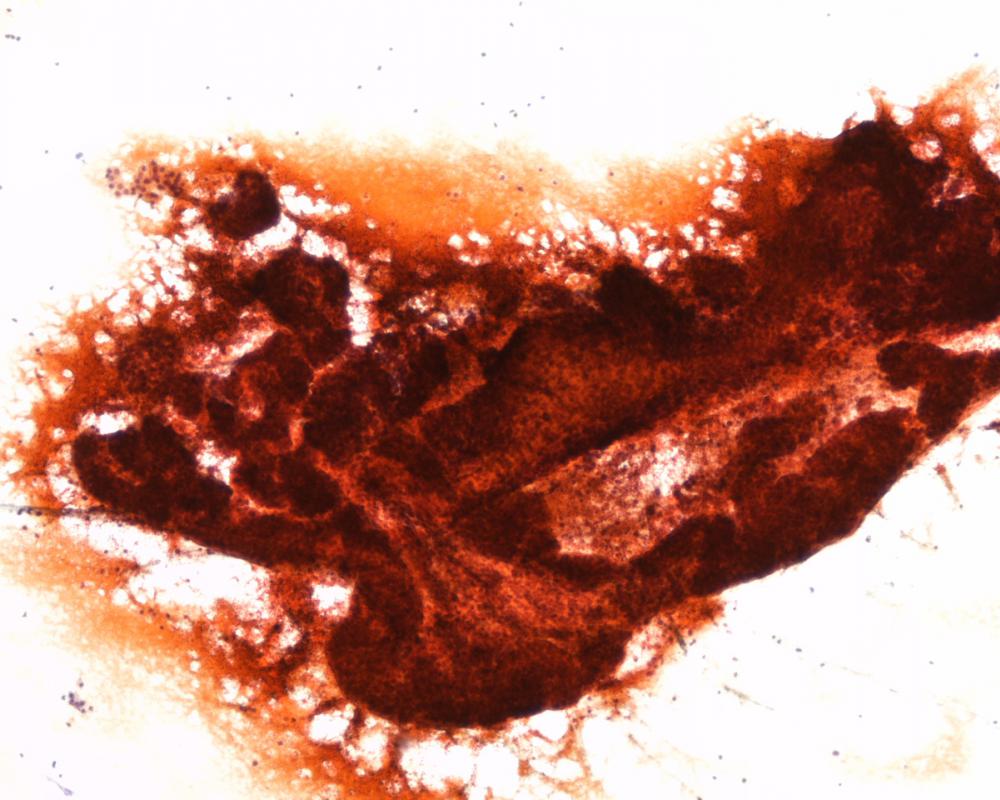

第34回日本臨床細胞学会九州連合会学会(長崎)スライドカンファレンス症例1

種別:婦人科

出題:鹿児島市立病院病理診断科 島尾 義也 先生

| 年齢 | 47歳 | 性別 | 女性 |

| 採取部位 | 子宮内膜 | 採取方法 | 吸引チューブ |

| 検体処理法 | 従来法 |

既往歴:特記すべきことなし

現病歴:2か月前から持続する性器出血を主訴に近医を受診。画像にて内膜肥厚を指摘され、当院産婦人科受診し内膜細胞診が施行された。

| 正解 | 1.子宮内膜腺間質破綻 |

| 1.子宮内膜腺間質破綻 | 43件 | (44.3%) | |

| 2.子宮内膜異型増殖症 | 26件 | (26.8%) | |

| 3.類内膜癌 | 22件 | (22.7%) | |

| 4.子宮内膜間質肉腫 | 1件 | (1.0%) | |

| 5.漿液性癌 | 5件 | (5.2%) | |

| 投票総数 | 97件 | (100%) |